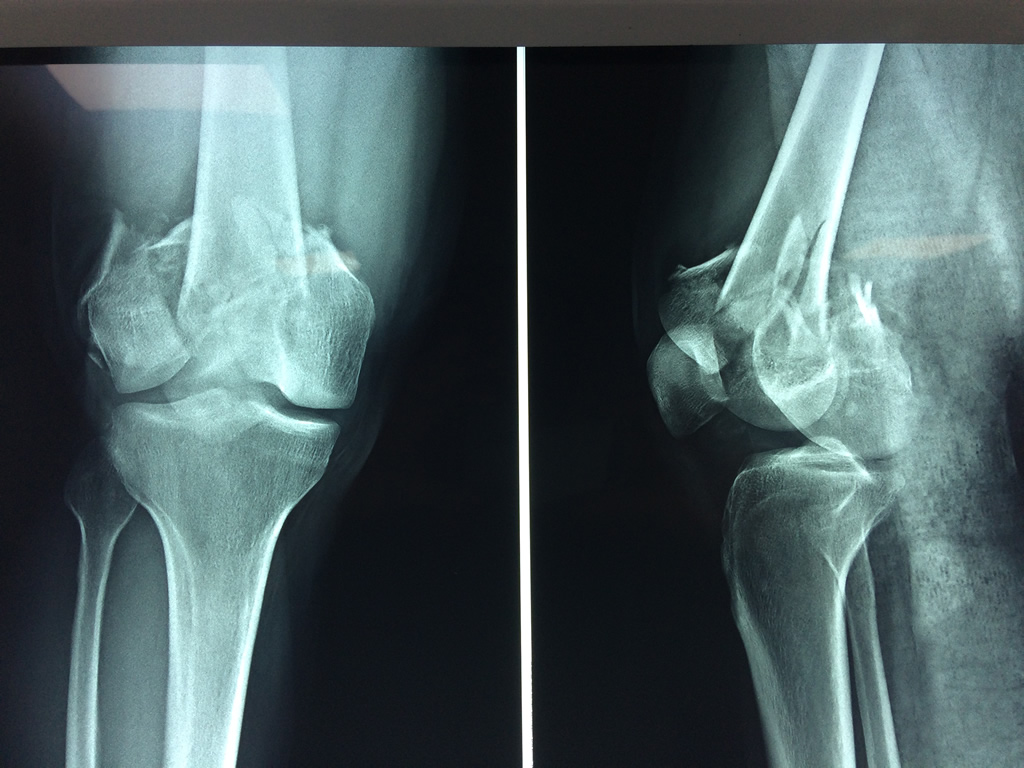

Cirugías de Codo - Fémur

El fémur es el hueso del muslo, el segundo segmento del miembro inferior. Es el hueso más largo, fuerte y voluminoso del cuerpo humano.